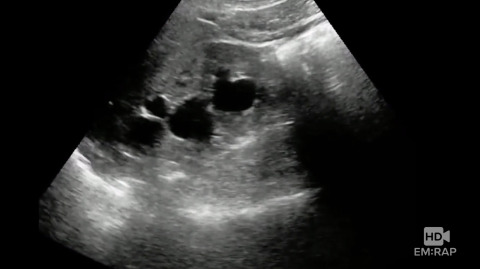

Ultrasound of Hydronephrosis

Dr. Jacob Avila reviews how to do an ultraound looking for hydronephrosis, a sign of an obstructing kidney stone. With mild hydronephrosis you see dilation of the renal pelvis and calyces. With moderate to severe hydronephrosis the renal parenchyma becomes compressed and disorted.